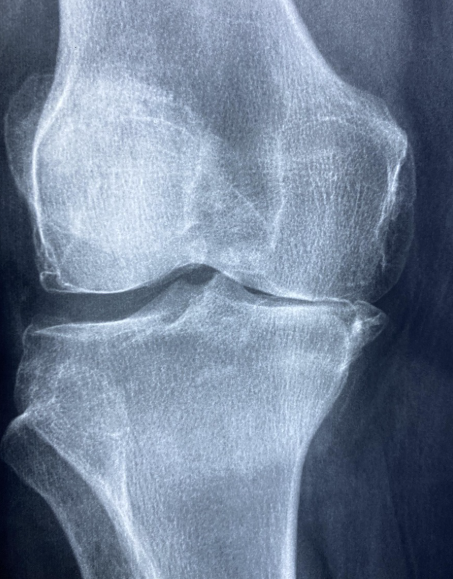

관절염은 관절을 보호하는 연골이 점차 마모되거나 손상되면서 염증이 발생해 통증과 운동 제한을 유발하는 질환입니다. 가장 흔한 형태는 퇴행성 관절염으로, 연골이 닳아 없어지면서 관절 내 충격을 흡수하지 못해 뼈와 뼈가 직접 맞닿게 되는 구조적 변화가 일어납니다. 이러한 변화는 노화 과정에서 자연스럽게 나타나기도 하지만, 최근에는 잘못된 생활습관과 환경적 요인으로 인해 비교적 젊은 연령층에서도 관절염 발병 사례가 꾸준히 증가하고 있습니다. 대표적인 원인으로는 과체중과 비만이 있습니다. 체중이 증가할수록 무릎과 고관절에 가해지는 하중이 커지며, 이는 연골 마모 속도를 가속화합니다. 장시간 앉아 있는 생활, 스마트폰과 컴퓨터 사용으로 인한 구부정한 자세, 반복적인 관절 사용 역시 관절에 지속적인 부담을 주는 요인입니다. 이외에도 과거의 외상이나 스포츠 손상, 선천적인 관절 구조 이상, 가족력, 호르몬 변화 등이 관절염 발생 위험을 높일 수 있습니다. 초기 관절염의 증상은 비교적 가볍게 나타나기 때문에 많은 사람들이 이를 대수롭지 않게 여기고 넘기는 경우가 많습니다. 아침에 일어났을 때 관절이 뻣뻣하게 느껴지거나, 움직이기 시작할 때 잠시 통증이 나타나는 것이 대표적인 초기 증상입니다. 계단을 오르내릴 때 무릎이 시큰거리거나, 장시간 보행 후 관절에 불편함이 생기기도 합니다. 이러한 통증은 휴식을 취하면 완화되는 특징이 있어 단순한 피로나 근육통으로 오인하기 쉽습니다. 그러나 이 시기에 적절한 관리가 이루어지지 않으면 연골 손상이 점차 누적되어 중기 관절염으로 진행될 가능성이 높아집니다.

관절염이 중기 단계로 접어들면 증상은 한층 더 뚜렷해집니다. 통증이 일시적으로 나타나는 것이 아니라 일상적인 활동 중 반복적으로 발생하며, 활동량이 많아질수록 통증의 강도도 점점 커집니다. 관절 주변이 눈에 띄게 붓거나 열감이 느껴지고, 관절을 움직일 때 뚝뚝 소리가 나는 경우도 흔하게 나타납니다. 이 단계에서는 연골이 상당 부분 손상되어 관절 간격이 좁아지고, 관절의 유연성과 안정성이 감소한 상태입니다. 중기 관절염 치료의 핵심 목표는 통증과 염증을 효과적으로 조절하고, 관절 기능 저하를 최대한 늦추는 데 있습니다. 가장 기본적인 치료 방법은 약물 치료로, 소염진통제를 사용해 통증과 염증을 완화합니다. 필요에 따라 연골 보호 성분이 포함된 약물이 병행되기도 합니다. 증상이 지속되거나 통증이 심한 경우에는 관절 주사 치료가 시행되며, 히알루론산 주사는 관절 내 윤활 작용을 도와 움직임을 부드럽게 하고 통증 완화에 도움을 줍니다. 물리치료와 재활운동 역시 중기 관절염 관리에서 매우 중요한 요소입니다. 관절 주변 근육을 강화하면 관절에 직접적으로 가해지는 부담을 줄일 수 있으며, 관절의 안정성을 높이는 데 도움이 됩니다. 허벅지 근육과 엉덩이 근육을 강화하는 운동은 무릎 관절 보호에 효과적입니다. 다만 무리한 운동은 오히려 관절 손상을 악화시킬 수 있으므로, 수영이나 실내 자전거와 같이 관절 부담이 적은 운동을 선택하는 것이 바람직합니다. 중기 단계에서의 꾸준한 치료와 관리 여부는 말기 관절염으로의 진행을 좌우하는 중요한 기준이 됩니다.

말기 관절염은 연골이 거의 소실되어 뼈와 뼈가 직접 마찰되는 상태로, 극심한 통증과 함께 관절 기능이 심각하게 저하됩니다. 가만히 있어도 통증이 지속되며, 밤에 통증으로 잠을 이루지 못하는 경우도 많습니다. 관절 변형이 눈에 띄게 나타나 보행이 어려워지고, 일상적인 활동조차 큰 불편을 겪게 됩니다. 이 단계에서는 약물이나 주사 치료만으로 충분한 효과를 기대하기 어렵습니다. 말기 관절염의 대표적인 치료 방법은 수술적 치료입니다. 관절 기능이 심각하게 손상된 경우 인공관절 치환술을 통해 통증을 제거하고 관절 기능을 회복할 수 있습니다. 최근에는 수술 기술과 인공관절 소재가 크게 발전하여 수술 후 회복 속도가 빨라지고, 내구성 향상되어 장기간 안정적인 사용이 가능합니다. 다만 수술은 신체적 부담이 따르기 때문에 환자의 상태와 연령, 생활환경 등을 종합적으로 고려하여 전문의와 충분한 상담 후 결정하는 것이 필요합니다. 무엇보다 중요한 것은 말기 단계까지 진행되지 않도록 예방 관리에 힘쓰는 것입니다. 관절염 예방의 핵심은 체중 관리입니다. 체중이 1kg 증가할 때마다 무릎 관절에는 그 이상의 하중이 가해지기 때문에, 적정 체중을 유지하는 것만으로도 관절염 위험을 크게 줄일 수 있습니다. 규칙적인 스트레칭과 근력 운동을 통해 관절 주변 근육을 강화하고, 장시간 같은 자세를 피하는 생활습관이 필요합니다. 관절에 통증이나 불편함이 느껴진다면 이를 참고 넘기지 말고 조기에 전문의 상담을 받는 것이 장기적인 관절 건강을 지키는 가장 효과적인 방법입니다.